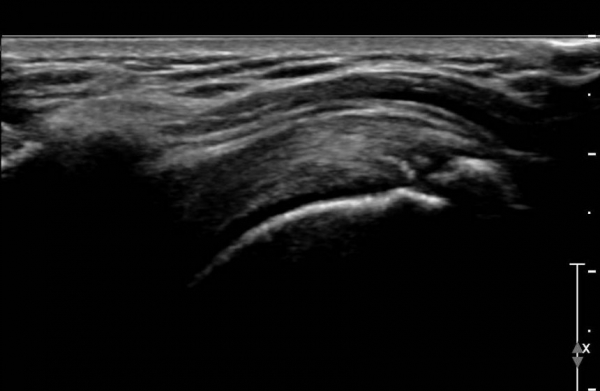

¼®È¸°¡ Å©°í ´Ü´ÜÇÑ °æ¿ì¿¡´Â ¼®È¸¸¦ ±ú´Â Ä¡·á¸¦ ½ÃÇàÇØ¾ßÇϴµ¥ ±¹¼Ò¸¶Ã븦 ½ÃÇàÇÏ°í ¼®È¸³»¿¡

ÁÖ»ç¿Í ÈíÀÎÀ» ¹Ýº¹ÇÏ´Â ¹æ¹ýÀ¸·Î ½ÃÇàÇÑ´Ù. ÷ºÎµ¿¿µ»ó 3¿¡¼­ º¸µíÀÌ ¹Ýº¹ÀûÀÎ ÁÖ»ç¿Í ÈíÀÎÀ¸·Î

´Ü´ÜÇÑ ¼®È¸°¡ Âɰ³Áö´Â °ÍÀ» º¼ ¼ö ÀÖ´Ù.